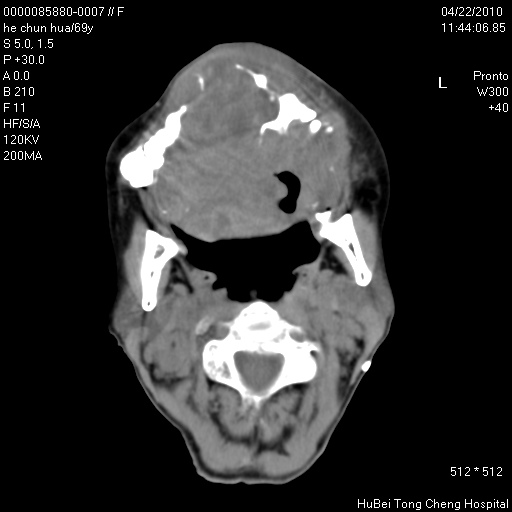

标题: CT25937:女,69Y

硬腭部包块十余年,渐进性增大。

不管以前,现在是恶性占位了

支持硬腭部恶性肿瘤!